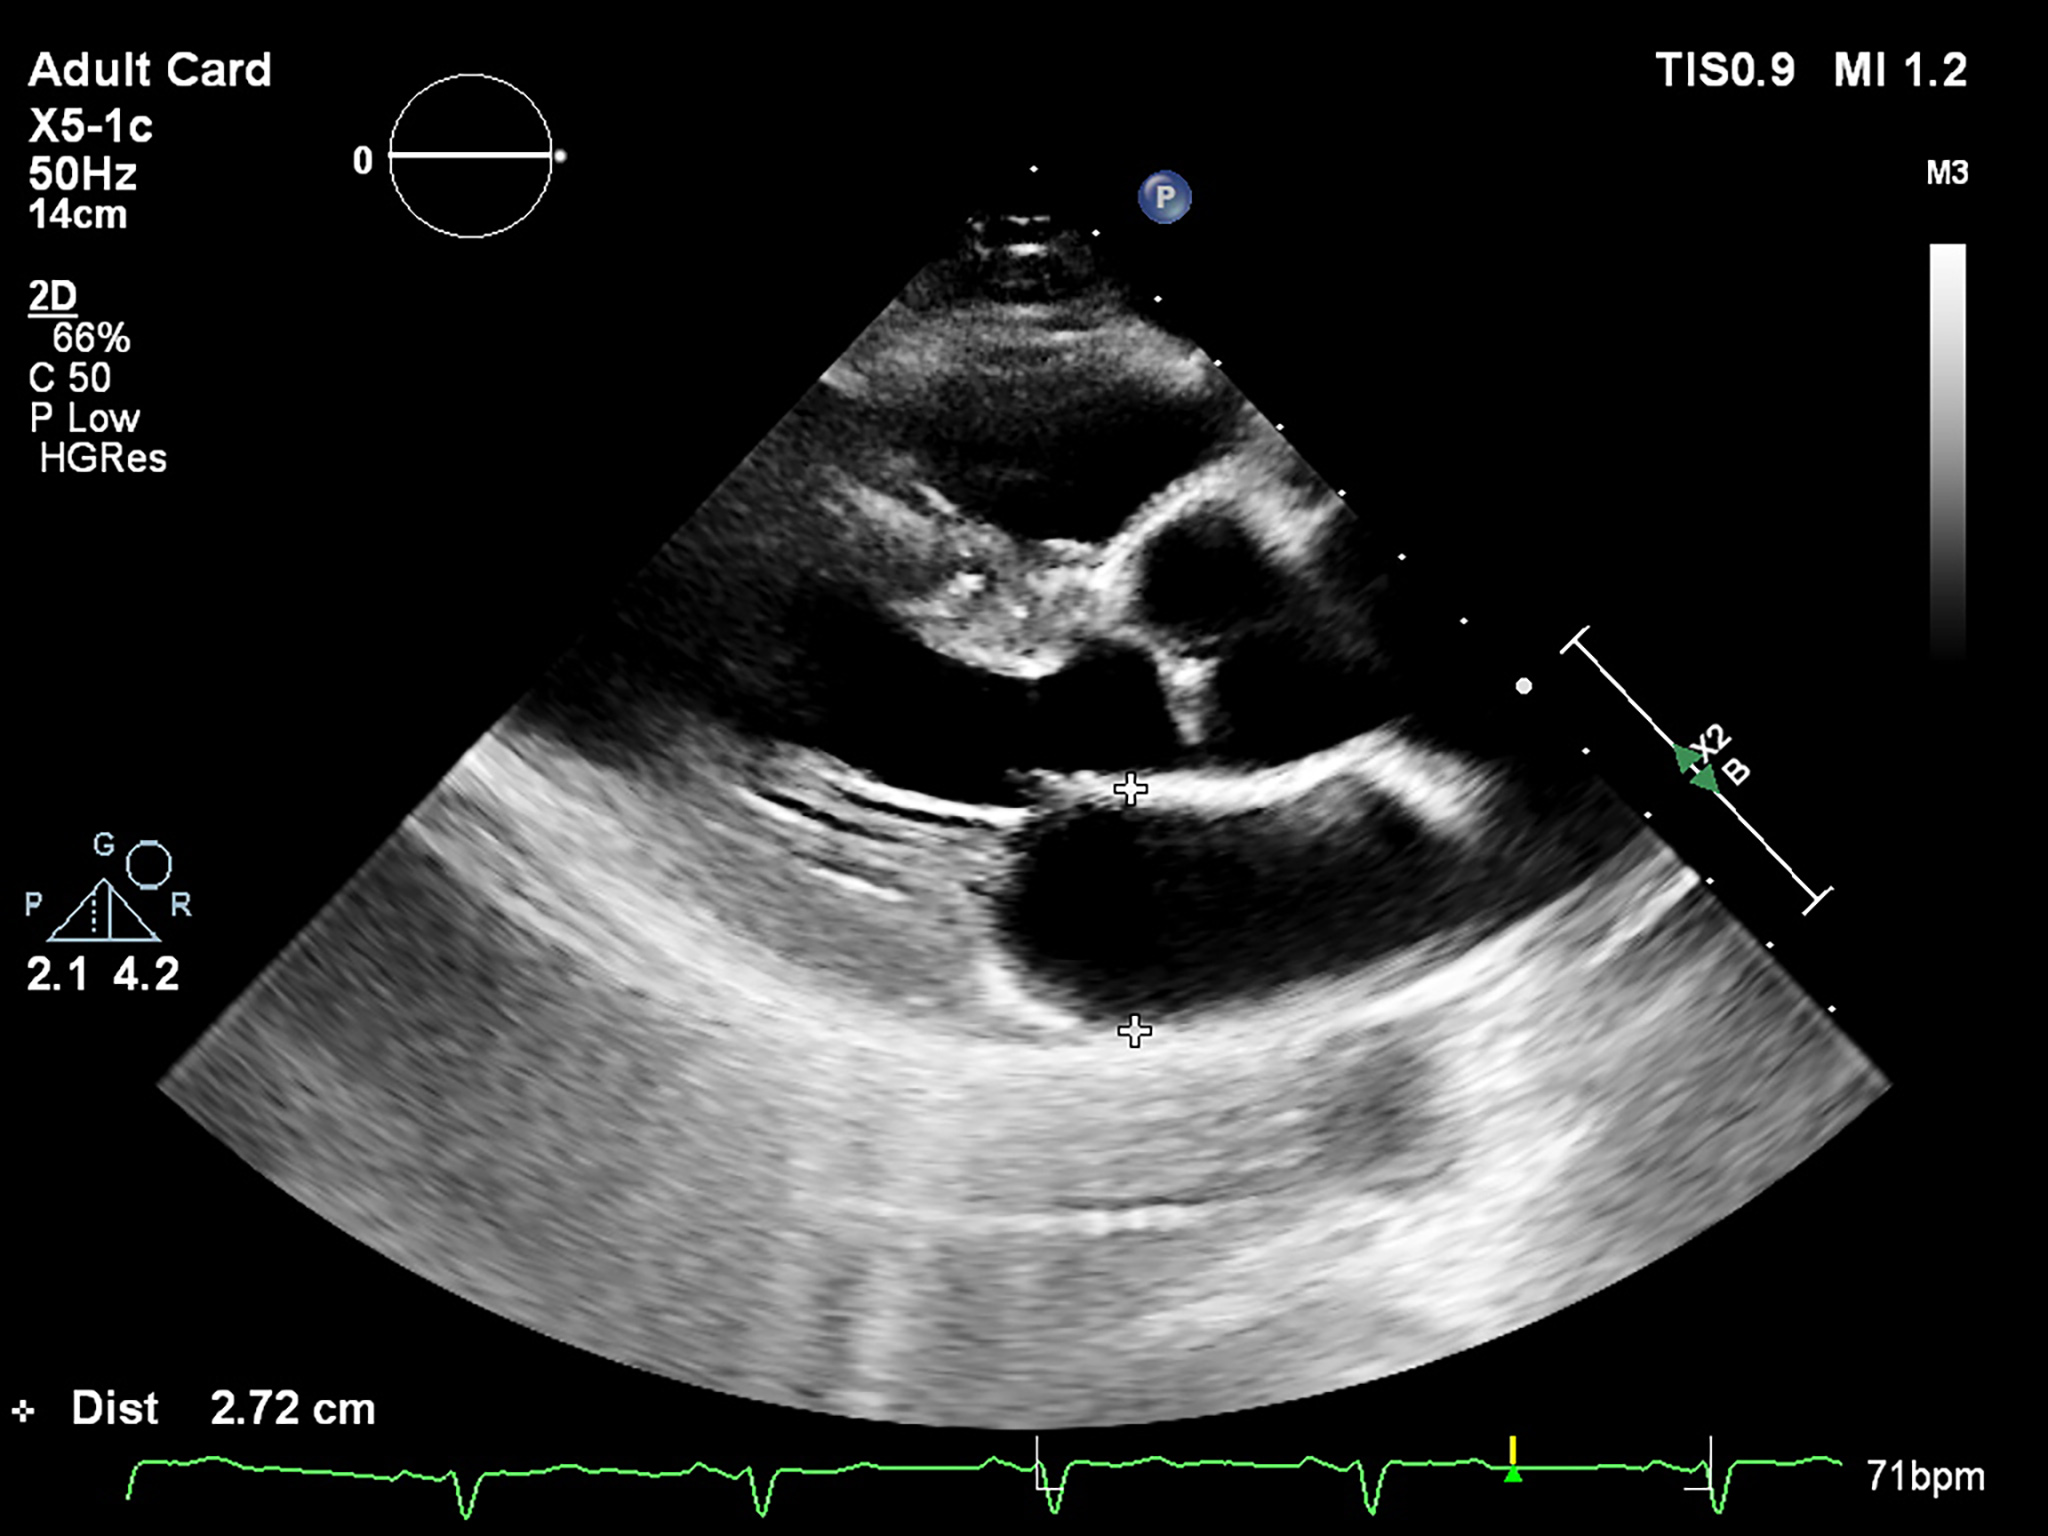

The LA antero-posterior (AP) diameter is the most evaluated parameter in patients with AF. The recommended measurement technique uses the long-axis view in bidimensional echocardiography (2D-E), perpendicular to the LA posterior wall, from inner edge to inner edge (Fig. 1). The latest chamber quantification recommendations suggest that the M-mode evaluation should no longer be used. The LA AP diameter was intensely evaluated in relation to AF development. An increased diameter, with a cut-off value of 40 mm, was associated with a higher risk of AF [22, 23]. This diameter should not be used solely, as it doesn’t represent the true LA size [24]. Moreover, the latest statements define a normal LA AP dimension less than 40 mm in males and 38 mm in females, with an indexed value of less than 23 mm in both genders [24].

Fig. 1.

Fig. 1.Measurement of the LA diameter (end-systole, inner edge to inner edge) in the parasternal long-axis view by bidimensional echocardiography.